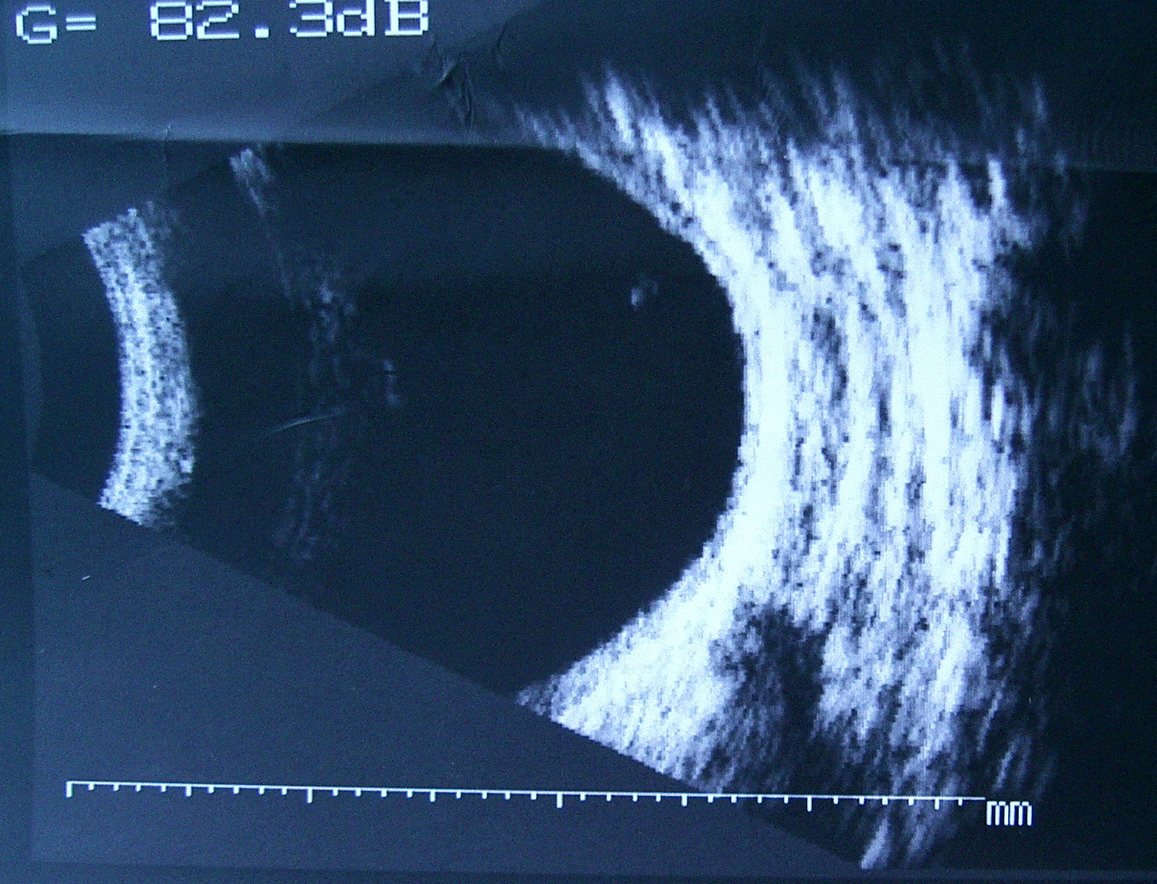

[B超]

B超: OD:眶未见明显异常回声区。 OS:眶鼻侧见边界不清,回声强弱不均之异常回声区。 意见: 右眼眶未见占位性病变声像。 左眼眶可疑占位性病变声像。建议CT进一步检查。